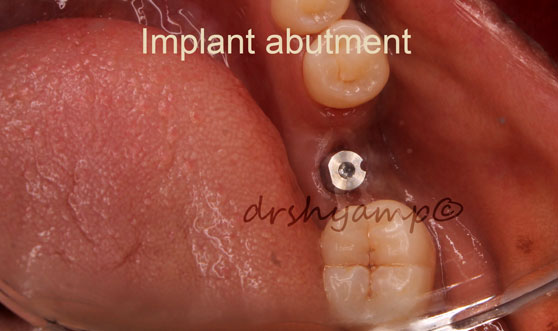

single molar dental implant

single molar dental implant

single molar dental implant

single molar dental implant

single molar dental implant

single molar dental implant

single molar dental implant

single molar dental implant

single molar dental implant

single molar dental implant

single molar dental implant

single molar dental implant

single molar dental implant

single molar dental implant

single molar dental implant